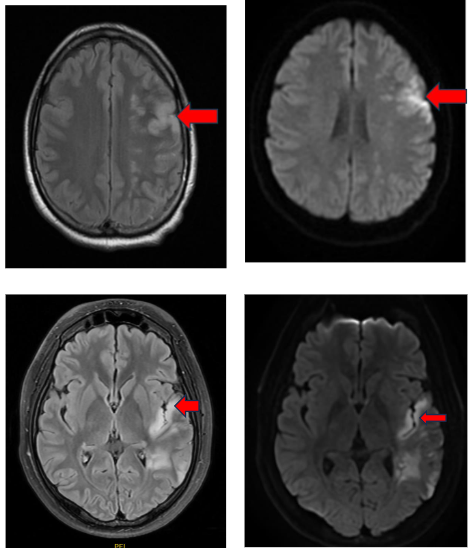

Aphasia was the most common clinical presentation, appearing in seven out of ten cases, with accompanying hemiparesis noted in four patients. Nine of the ten patients with primary APS experienced strokes in the M2 segment of the middle cerebral artery, predominantly resulting in peri-sylvian infarcts.

With a notable prevalence in the left peri-sylvian region (6 out of nine patients). Only one patient presented with a posterior circulation stroke, exhibiting a top of basilar syndrome. CT angiography revealed a left M2 occlusion in one case and distal basilar occlusion in another, while the remaining cases had no significant angiographic findings. 2D Echo was normal in all patients. TEE was done in 3 patients, which was normal. Holter study was normal in all patients.

The clinical and radiological profile of ischemic strokes associated with APS, as observed in this case series, reveals distinctive patterns in symptomatology and imaging that reinforce previous studies yet also highlight unique characteristics. The predominance of peri-sylvian infarcts in the M2/M3 segments of the middle cerebral artery, especially affecting the left hemisphere, aligns with findings that cortical strokes with aphasia as the primary presentation are often linked to embolic strokes. Studies have similarly observed that ischemic events in APS patients tend to exhibit neuroimaging patterns indicative of embolic mechanisms, often resembling cardioembolic stroke distributions. This correlation emphasizes the role of APS as a prothrombotic condition with implications for early detection and management of stroke in young patients, regardless of traditional vascular risk factors.

Recent studies emphasize the importance of specific MRI findings in diagnosing APS-related CNS involvement. Graf (2017) underscores the role of MRI in detecting small, scattered ischemic lesions, often located in cortical and subcortical regions, which are indicative of embolic phenomena. These findings align with the peri-sylvian infarct patterns noted in this case series.

Advanced imaging techniques, such as diffusion-weighted imaging (DWI), provide additional diagnostic value. DWI often reveals acute ischemic lesions in multiple vascular territories, which are characteristic of APS-related strokes and highlight the embolic origin associated with aPLs.

White matter hyperintensities (WMHs) on T2-weighted MRI are also frequently observed in APS patients, even among those without conventional vascular risk factors. Zhao et al. (2024) suggest integrating vessel wall imaging and perfusion studies into routine practice to enhance diagnostic accuracy.